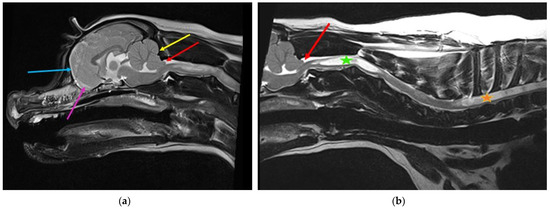

CSF passes from the ventricular to the subarachnoid space via the lateral apertures of the fourth ventricle (in humans, referred to as the foramen of Luschka). Primates have an additional foramen of Megendie in the median plane between the fourth ventricle and cisterna magnum [67]. In species other than primates, the fourth ventricle and cisterna magna are separated by the caudal medullary velum [67]. The authors hypothesize that a reduced caudal cranial fossa volume in some brachycephalic breeds results in obstruction of this CSF pathway, contributing to the tendency for ventriculomegaly and syringomyelia (Figure 2).

Figure 2.

Possible lateral aperture obstruction in a three-year-old Boston terrier with ventriculomegaly and early syringomyelia. (a) T2-weighted midsagittal brain. There is dilatation of the lateral (blue star), third (pink arrow), and fourth ventricle (blue arrow) with syringomyelia (green arrow). There is hyperdynamic flow of the CSF in the region of the obex, as evidenced by the hypointense fluid void sign (yellow arrow). The bulging caudal medullary velum can be appreciated (red arrow). There is marked reduction of the olfactory bulbs (white arrow), with ventral rotation of the brain because of brachycephaly, in addition to reduction of the nasal cavity. Consequently, reduced absorption of CSF through the olfactory lymphatics is suspected. (b) T2-weighted transverse brain at the level of the lateral aperture of the fourth ventricle (yellow arrows). The Boston Terrier in (a) is on the left and a normal brachycephalic dog on the right. The lateral apertures in the Boston Terrier cannot be appreciated. There is an absence of hyperintense CSF, and obstruction of these CSF pathways are suspected (images created by C. Rusbridge and S.P. Knowler).